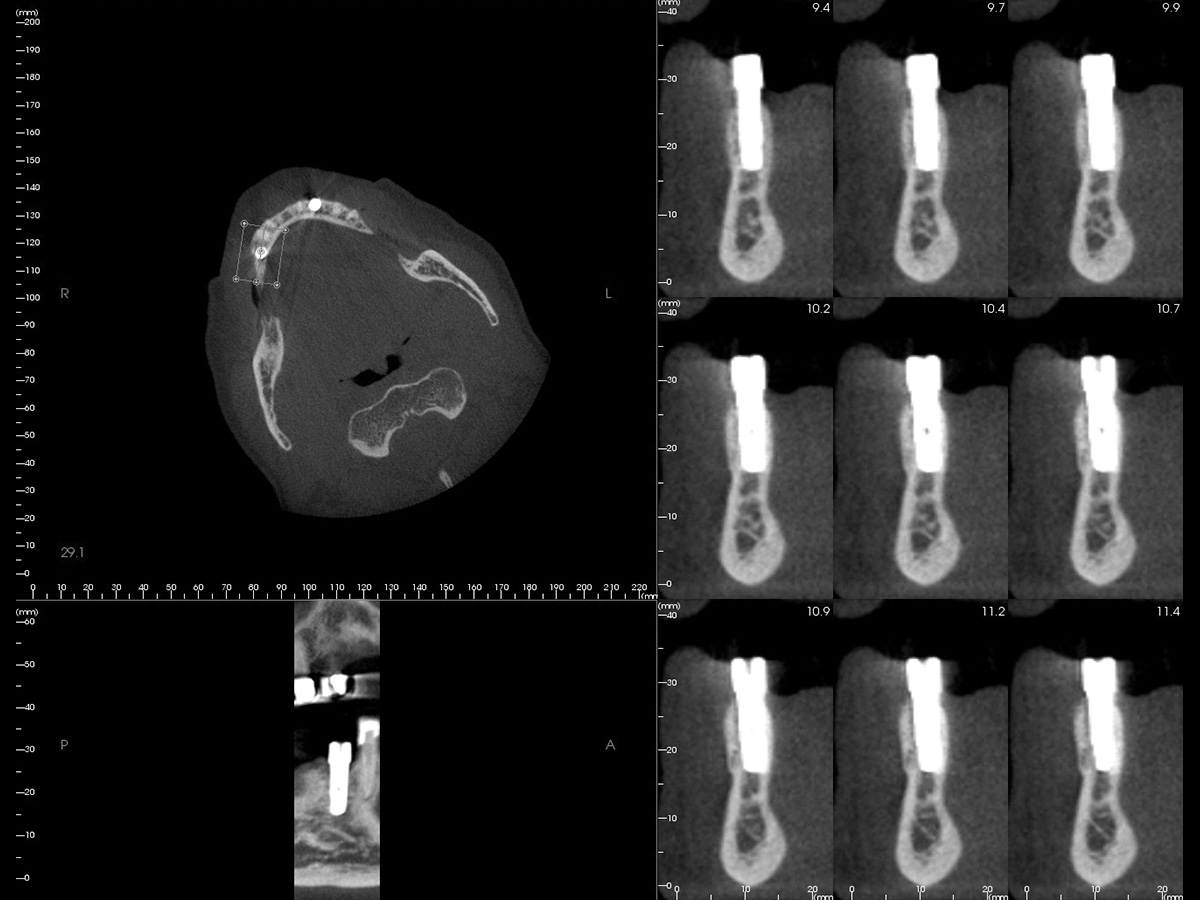

Abbildung 2

DVT mit Implantatplanung zeigt die atrophe Knochensituation mit geplantem Implantat.